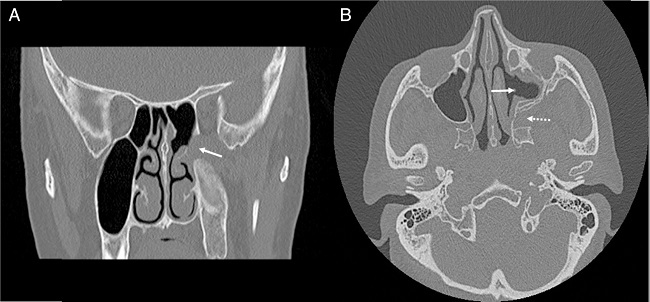

Endoscopic endonasal resection of the vascular lesion was performed under general anesthesia, without any complications. In operation, first, the medial wall of the maxillary sinus was removed and wide antrostomy was made. Anterior and posterior ethmoidectomy was added for increased visualization to posterior portion of the maxillary sinus. After that, sphenoidotomy was made and opticocarotid recess was identified for evaluation of the relationship with cavernous sinus. Posterior wall of the maxillary sinus was removed partially and the tumor was seen in PPF (Fig. 3). At this stage, sphenopalatine artery was cauterized against the possibility of bleeding. Finally, the tumor was dissected from near anatomical structures with bipolar cautery and excised totally. Histopathological examination was reported as cavernous hemangioma (Fig. 4).

The surgical approach to Pterygopalatine Fossa (PPF) is difficult, for anatomical reasons (Fig. 5). The PPF is located anterior to the pterygoid plates, posterior to the maxillary sinus and inferior to the middle cranial fossa. PPF mostly includes lesions arising from skull base, nasal and oral cavity and orbit. In differential diagnosis, numerous diseases must be kept in mind for PPF masses, such as epidermoid cyst, meningoceles, carcinomas, melanomas, schwannomas, neurofibromas, neurofibrosarcomas, chordomas, and teratomas.7 Standard surgical approach to the PPF is Caldwell-Luc procedure. However, this technique offers a limited intraoperative view and requires gingivobuccal sulcus incision. Also, it is associated with some complications, such as recurrent sinusitis, pain or numbness on the face and teeth, facial swelling and infraorbital nerve and vessels injury.8,9